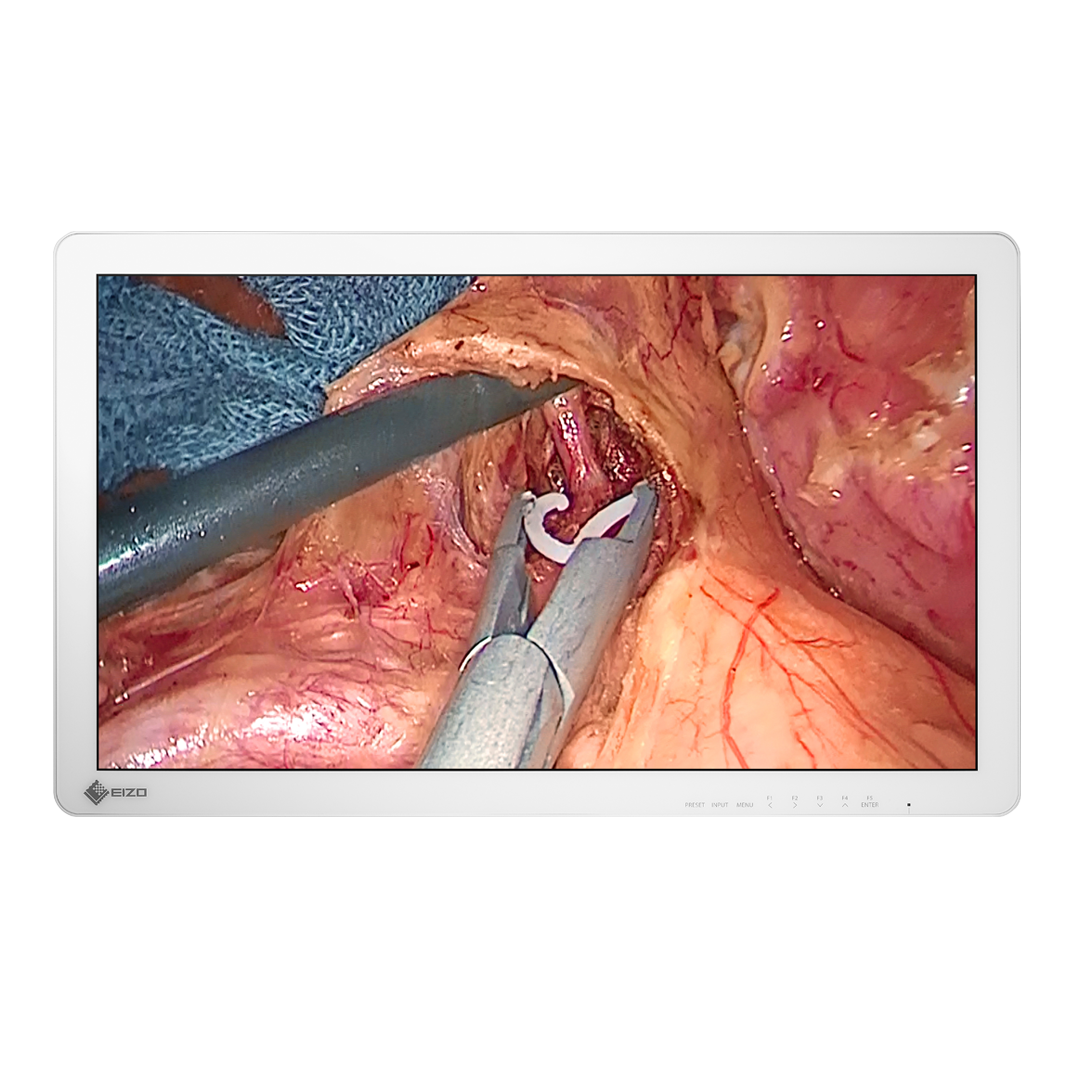

Seria CuratOR

Seria EIZO CuratOR oferuje z kolei rozwiązania na nowoczesne sale operacyjne. Zaprojektowano je tak, aby były łatwo skalowalne i odpowiadały zróżnicowanym potrzebom zespołów chirurgicznych.